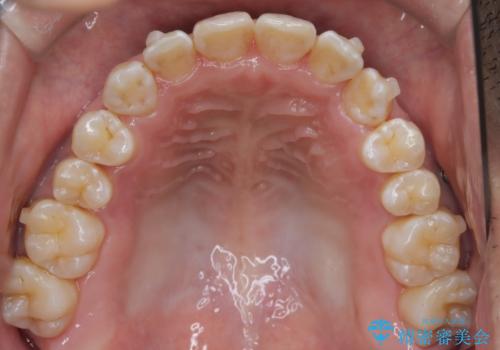

- 左上の八重歯を気にされて来院されました。精密な検査の結果、歯列全体を広げながら八重歯を奥へ移動させることで、美しい歯並びと機能的な咬み合わせが得られると診断。患者様のご希望に合わせ、透明で目立ちにくい**インビザライン(マウスピース矯正)**による治療計画を立案しました。抜歯を避け、歯を少しずつ遠心(奥)へ移動させることで、歯が並ぶスペースを確保し、叢生(歯のデコボコ)を改善します。

今回の矯正治療では、透明なマウスピース型の装置インビザラインを使用しました。この装置は目立ちにくく、取り外しが可能なため、食事や歯磨きも普段通りに行えます。遠心移動という方法で奥歯を後方に動かし、前歯を並べるためのスペースを確保。これにより、抜歯することなく、左上の八重歯を含む叢生を効果的に改善し、整った美しい歯並びと良好な咬み合わせを獲得していただけました。